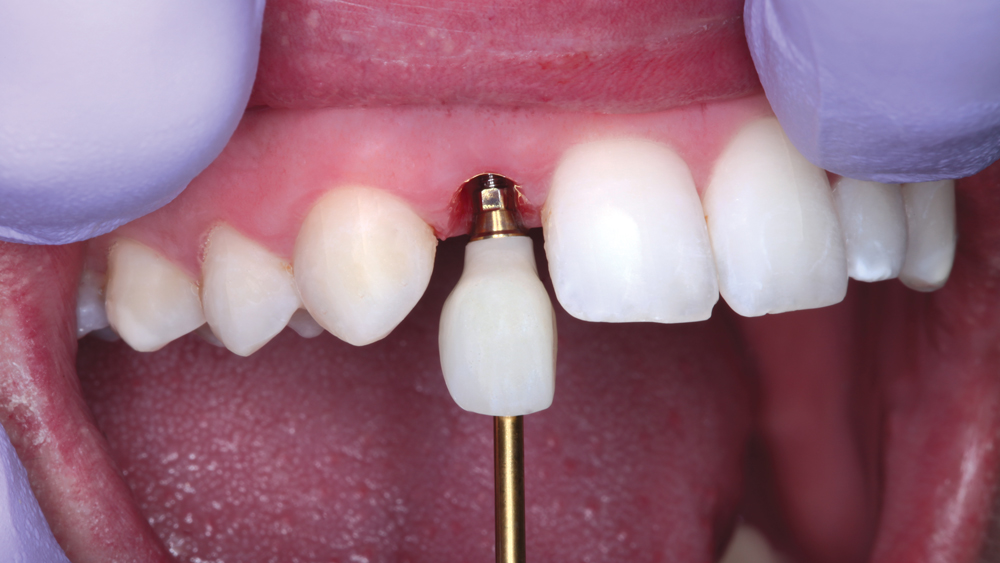

The following case illustrates the efficient, straightforward clinical workflow for placing Hahn Tapered Implants via guided surgery. A digital treatment plan is developed in which a 3.5 mm implant is positioned to support the ideal prosthetic outcome. An immediate provisional crown is designed in concert with the surgical guide and delivered at the time of surgery, helping to produce a predictable, highly esthetic restoration for a demanding case in the smile zone.